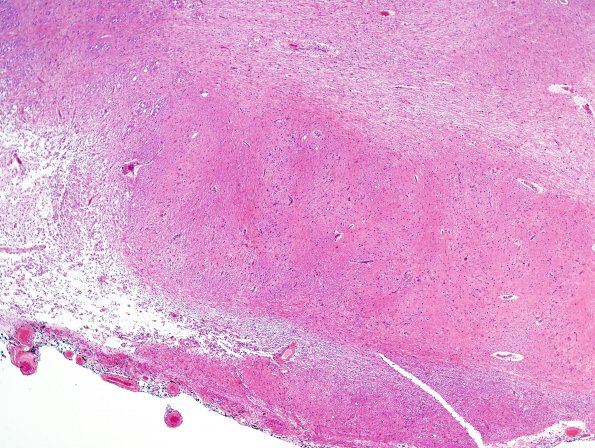

Washington University Experience | BASIC PROCESSES | Olivary Hyperplasia | 10C2 Infarcts, multiple, Olive HT (Case 12) H&E 1

10C2,3 The inferior aspect of the right ION (arrow, 10C1 and at higher magnification in 10C2) and the superior aspect of the right ION (arrowhead, 10C1 and in image #10C3) differ in the presence of enlarged multivacuolated neurons (H&E).